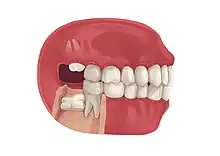

Impacted wisdom teeth is a condition where the third molars (wisdom teeth) are prevented from erupting into the mouth.[1] This can be caused by a physical barrier, such as other teeth, or when the tooth is angled away from a vertical position.[2] Completely unerupted wisdom teeth usually result in no symptoms, although they can sometimes develop cysts or neoplasms. Partially erupted wisdom teeth or wisdom teeth that are not erupted but are exposed to oral bacteria through deep periodontal pocket, can develop cavities or pericoronitis. Removal of impacted wisdom teeth is advised for the future prevention of or in the current presence of certain pathologies, such as caries (dental decay), periodontal disease or cysts. Prophylactic (preventative) extraction of wisdom teeth is preferred to be done at a younger age (middle to late teenage years) to take advantage of incomplete root development, which is associated with an easier surgical procedure and less probability of complications.[3]

Impacted wisdom teeth are classified by their direction of impaction, their depth compared to the biting surface of adjacent teeth and the amount of the tooth's crown that extends through gum tissue or bone. Impacted wisdom teeth can also be classified by the presence or absence of symptoms and disease. Screening for the presence of wisdom teeth often begins in late adolescence when a partially developed tooth may become impacted. Screening commonly includes a clinical examination as well as x-rays such as panoramic radiographs.

Impacted wisdom teeth are often described by the direction of their impaction (forward tilting, or mesioangular being the most common), the depth of impaction and the age of the patient as well as other factors such as pre-existing infection or the presence of pathology (cysts, tumors or other disease).[5]: 143–144 Each of these factors is used to predict the difficulty (and rate of complications) when removing an impacted tooth, with age being the most reliable predictor[8] rather than the orientation of the impaction.[9]